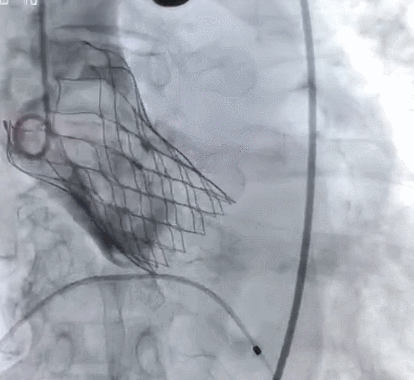

术后造影